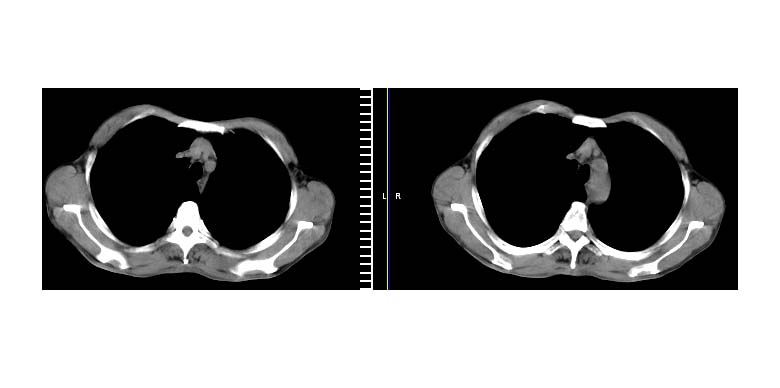

标题: CT11019:男性,66岁。发烧5-6天。治疗后无明显好转。 [打印本页]

标题: CT11019:男性,66岁。发烧5-6天。治疗后无明显好转。

支持抗炎后复查,无明显肿大淋巴结,胸膜也无改变

左下肺中心性肺癌伴下肺不张及周围阻塞性炎症,

建议:支气管镜检查。

左肺门下分增大见有结节影,基底干及分支显示不清,下叶体积缩小,呈片带状机磨玻璃样影显示。支持考虑左下肺中心型肺癌伴阻塞性肺炎及部分肺不张。建议纤支镜检查

先做增强扫描,然后建议支纤镜活检或ct引导下穿刺活检,